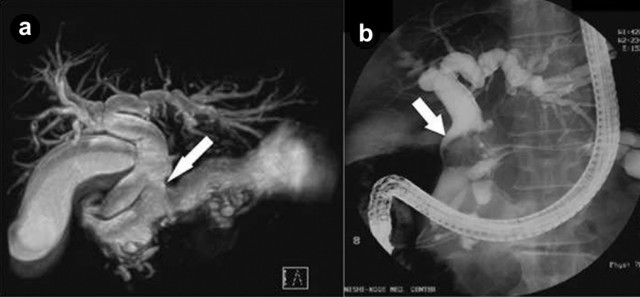

Two and a half years after the first admission, he reported jaundice and serum bilirubin concentration was elevated (4.5 mg/dL; reference range: 0.2-1.2 mg/dL). CT and MRI revealed dilation of intrahepatic bile duct and the branch duct of the pancreas penetrating to the common bile duct (Figure 4a). Endoscopic retrograde cholangiopancreatography (ERCP) was performed, revealing filling defect in the middle common bile duct, which consisted of mucus discharged from the fistula (Figure 4b). Endoscope biliary drainage by stent placement was performed to alleviate the obstructive jaundice. However, the stent slipped out of the bile duct automatically. It was probably because of the viscosity of the mucus in the bile. Percutaneous biliary drainage or choledochojejunostomy could have alleviated the jaundice, but he refused any further treatments. He had recurrent cholangitis due to cholestasis, which oral levofloxacin was effective to ameliorate. Despite jaundice and recurrent cholangitis, he is still ambulatory and seen in the clinic three years after the first admission.

Figure 4. a. Magnetic resonance cholangiopancreatography (MRCP) showed the branch duct of the pancreas penetrating to the common bile duct (arrow) and dilated intrahepatic bile duct. b. Endoscopic retrograde cholangiopancreatography (ERCP) showed filling defect in the middle common bile duct (arrow), which consisted of mucus discharged from the fistula. |